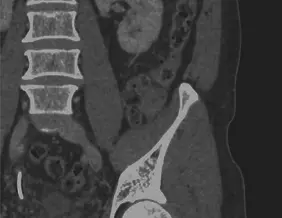

PEARLS AND PITFALLS OF STRUCTURED STAGING AND REPORTING OF RECTAL CANCER ON MRI: AN INTERNATIONAL MULTIREADER STUDY

Uniformity to diagnose high-risk (≥cT3 ab) versus low-risk (≤cT3 cd) cT-stage, cN0 versus cN+, lateral nodes and tumour deposits, MRF and sphincter involvement, and solid versus mucinous tumours was high with IOA > 80% in the majority of cases (and >80% agreement with expert consensus). Results for assessing extramural vascular invasion, cT-stage (cT1-2/cT3/cT4a/cT4b), cN-stage (cN0/N1/N2), relation to the peritoneal reflection, extent of sphincter involvement (internal/intersphincteric/external) and morphology (solid/annular/semi-annular) were considerably poorer. IOA was high (α = 0.72–0.84) for tumour height/length and extramural invasion depth, but low for tumour-MRF distance and number of (suspicious) nodes (α = 0.05–0.55). There was a significant positive correlation between diagnostic confidence and accuracy (=agreement with expert consensus) (p < 0.001-p = 0.003).